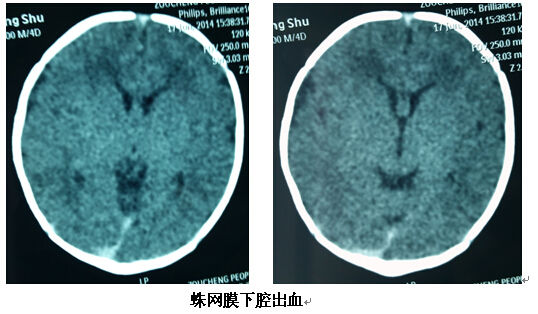

原发性蛛网膜下腔出血是指出血原发部位在蛛网膜下腔。此类型出血在新生儿期十分常见,出血量很少,没有临床征象,仅仅有轻微的表现,比如容易哭闹等,多于一周内恢复,经常是在其他原因做影像学检查时发现,预后良好。如果有这样的情况,家长不用着急,出血部位的少量血液很快会被吸收,不会留任何后遗症,也不需要再做头颅影像学检查,更不需要任何治疗和康复。